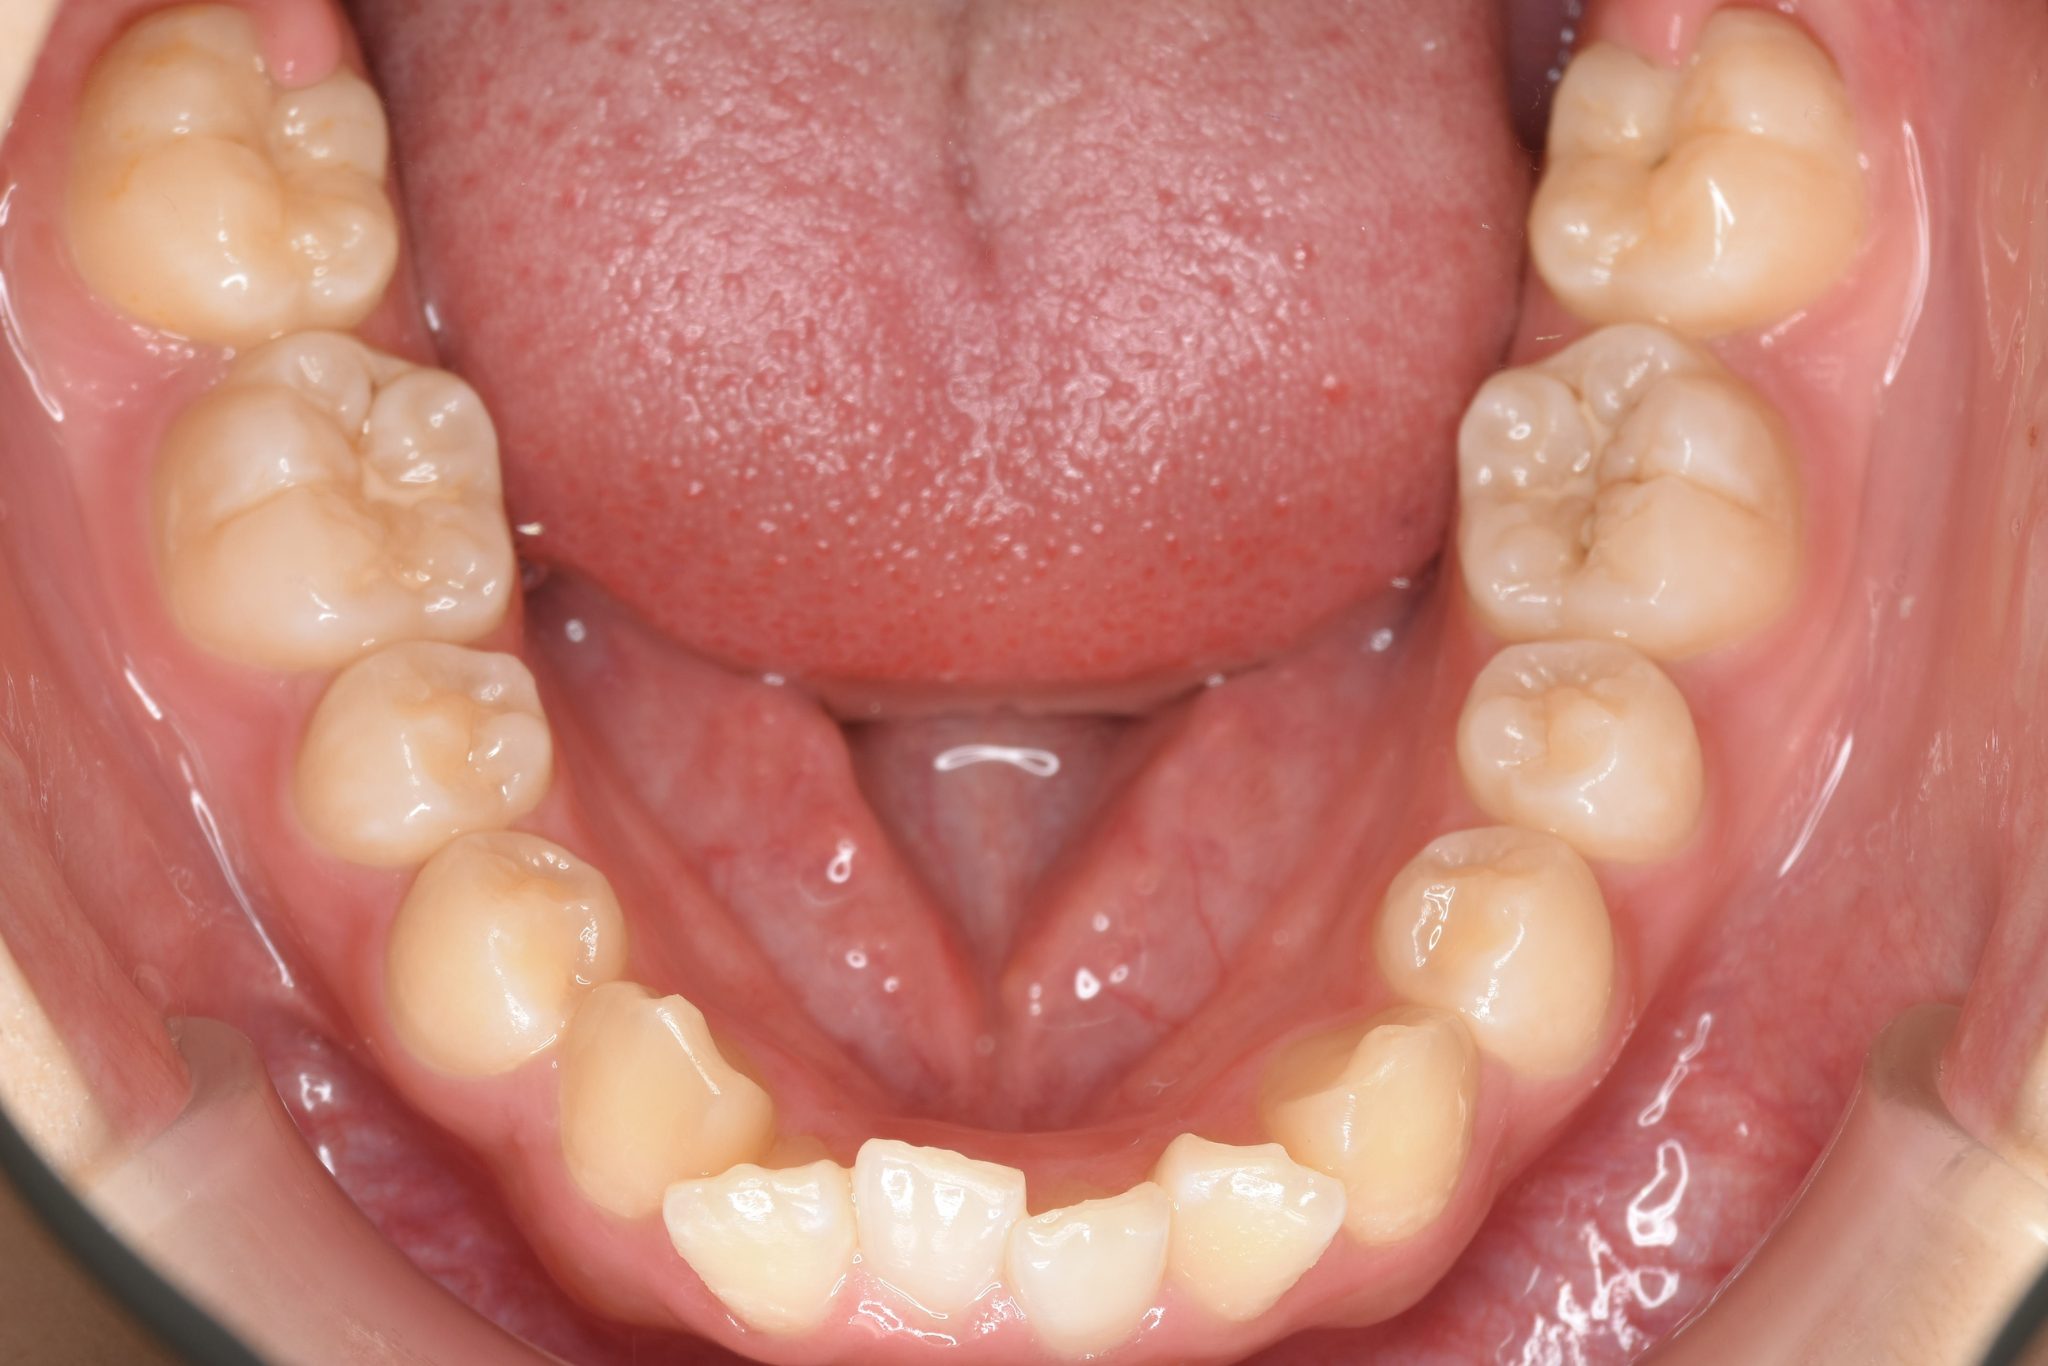

ビフォー

全顎ワイヤー矯正 症例_805